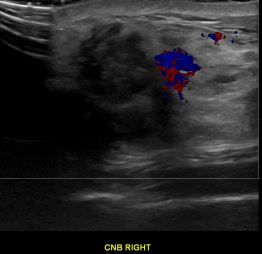

상기환자는 우측 유방 만져지는 멍우리와 통증있어  내원하신 40대중반 여성분으로 의심스러운 우측혹 조직검사 시행해 유방암으로 진단되었습니다